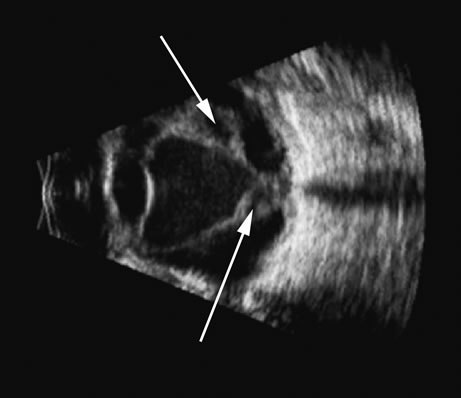

Fig. 17. This patient with a Molteno tube was treated for glaucoma. The top 50 MHz B-scan clearly shows the Molteno Tube (arrow). The bottom 10 MHz B-scan of the same patient demonstrates a choroidal detachment (large arrow) with associated posterior retinal detachment (small arrow). Choroidal elevations are typically convex, highly reflective surfaces with posterior limitation at the vortex vessels. Retina will always attach at the optic nerve. Choroidal elevations are often noted in several quadrants, as seen here.